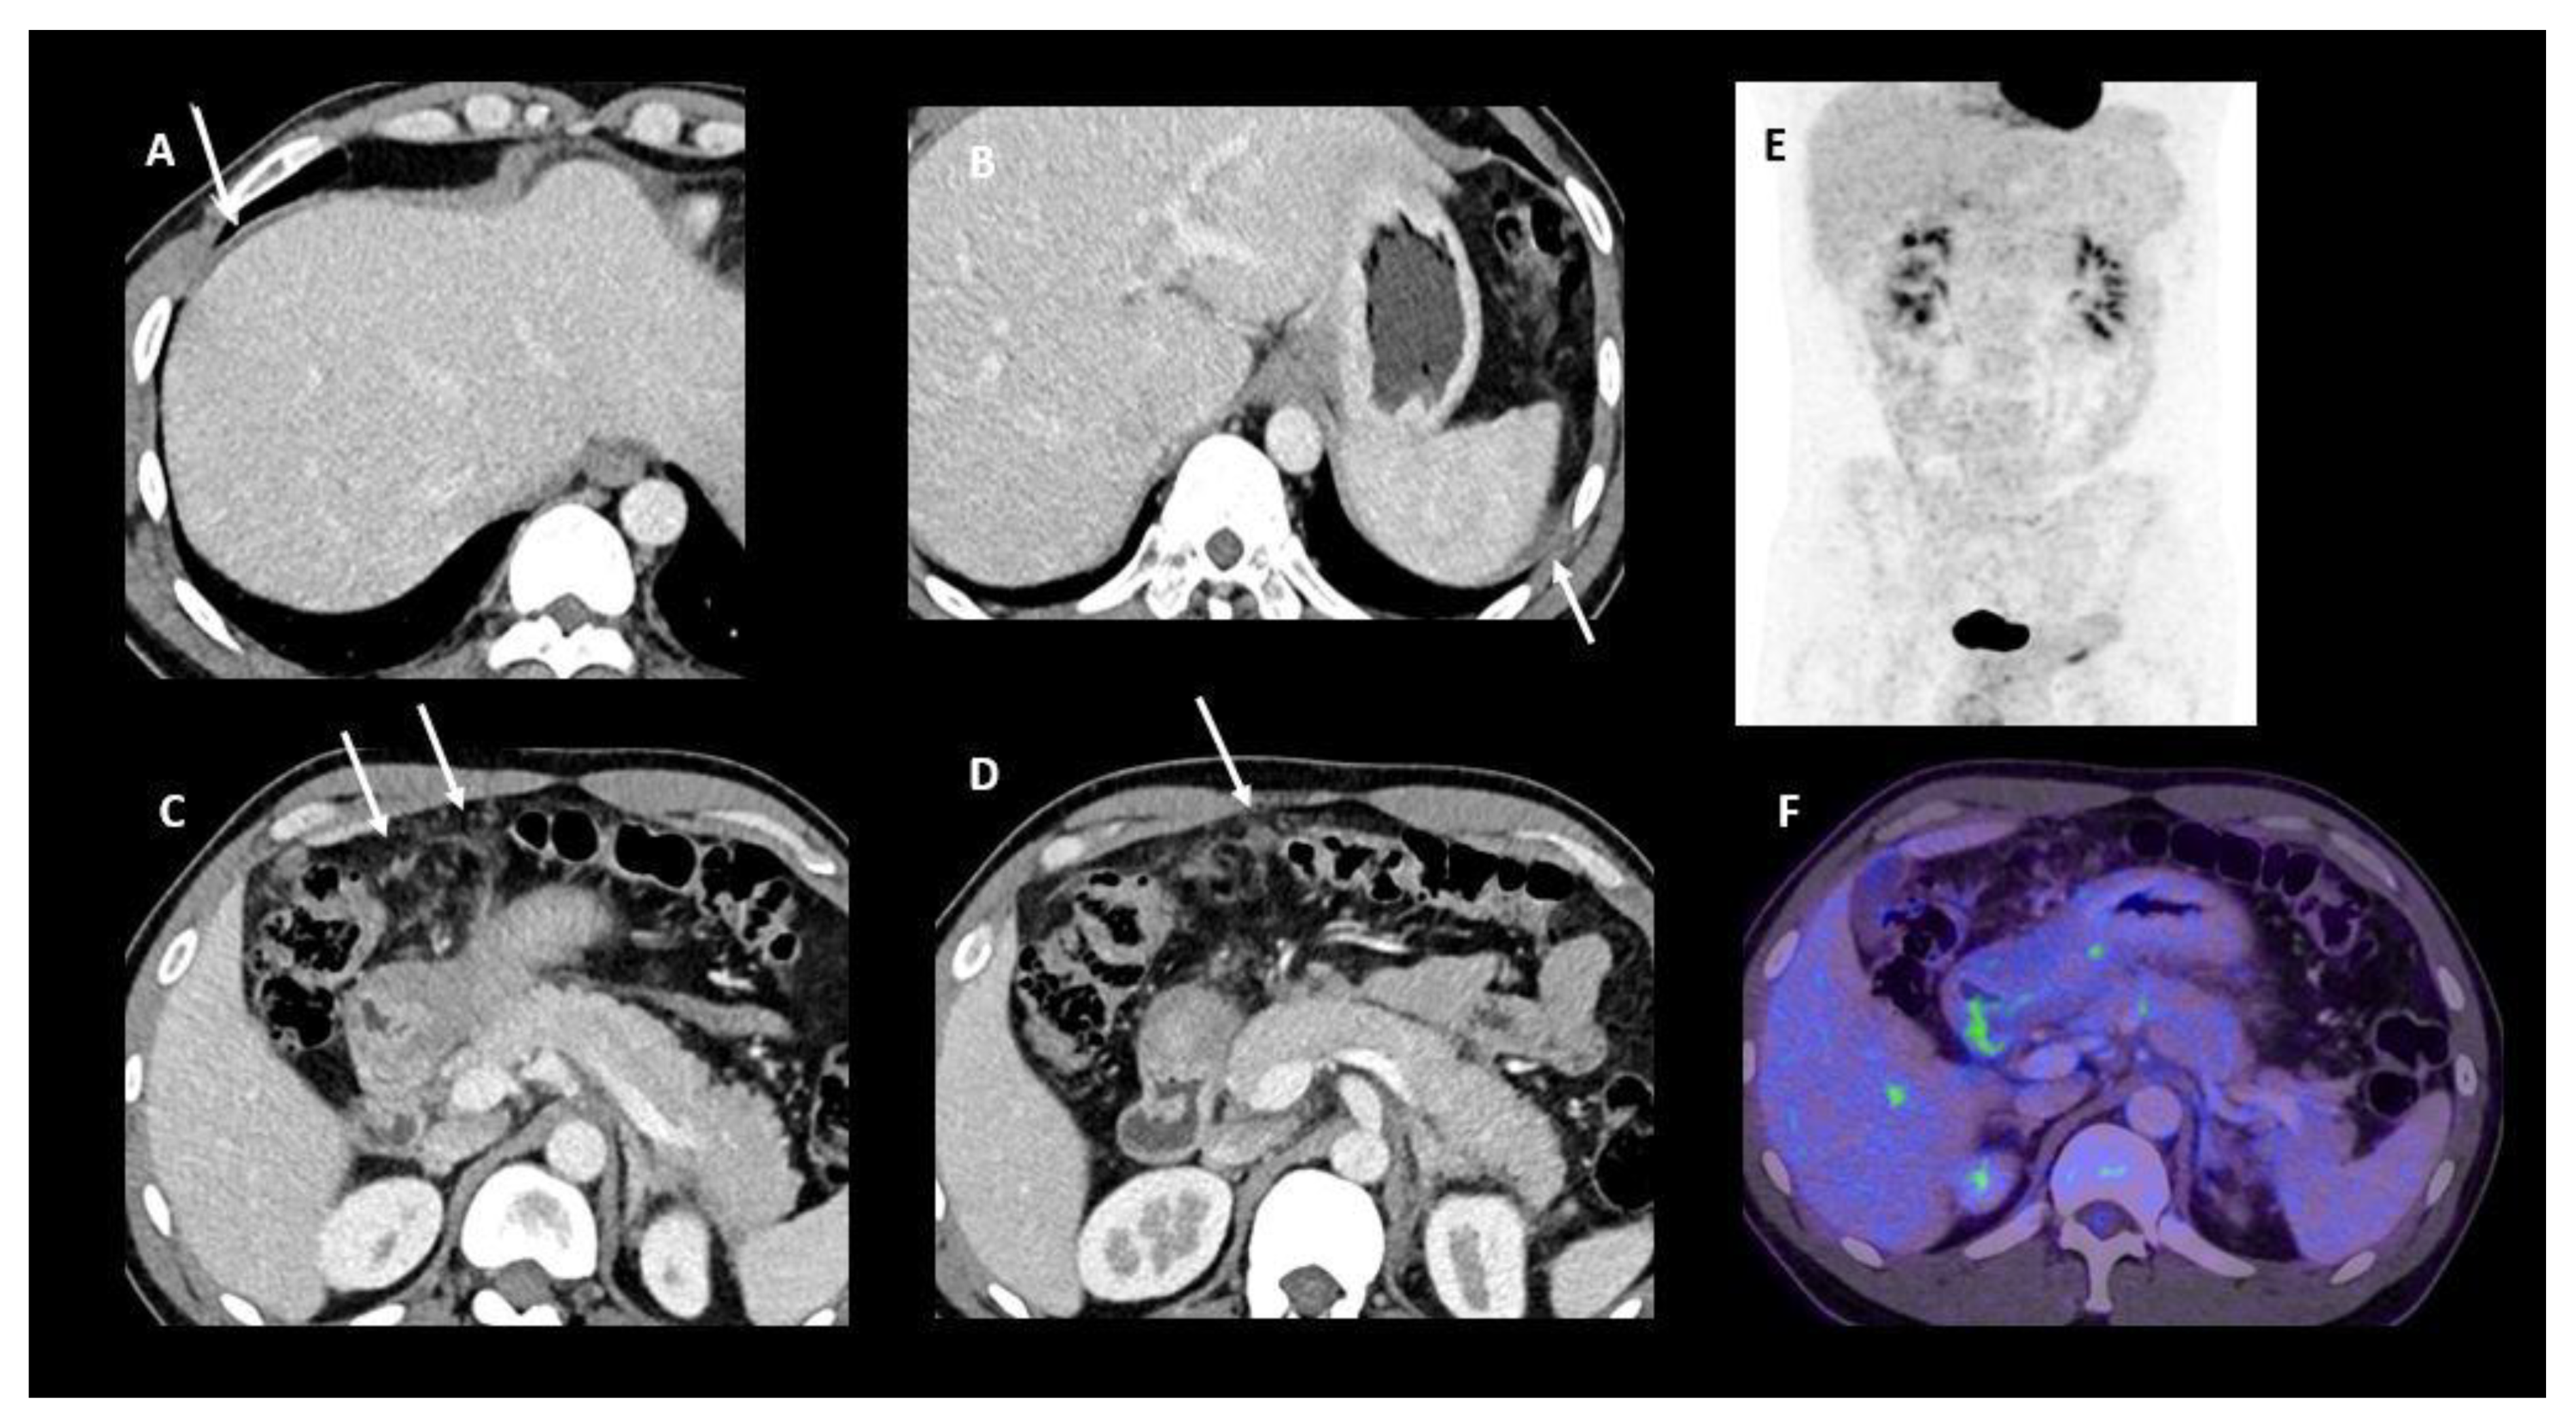

- Sugarbaker, P.H.; Sardi, A.; Brown, G.; Dromain, C.; Rousset, P.; Jelinek, J.S. Concerning CT features used to select patients for treatment of peritoneal metastases, a pictoral essay. Int. J. Hyperth. 2017, 33, 497–504. [Google Scholar] [CrossRef] [PubMed]

| Bowel obstruction or partial obstruction at more than one site |

| Mesentery drawn together by tumour (clumped bowel) |

| Tumour infiltrating between leaves of the small bowel mesentery |

| Tumour ≥ 5 cm in diameter in jejunal regions |

| Mesenteric or para-aortic lymphadenopathy |

| Hydroureter |

| Psoas muscle invasion |

| Pelvis sidewall invasion |

| Seminal vesicle invasion |

| Hepatoduodenal ligament infiltration and/or bile duct obstruction |

| Tumour ≥ 5 cm in diameter in gastrohepatic ligament or subpyloric space |

| Gastric outlet obstruction |